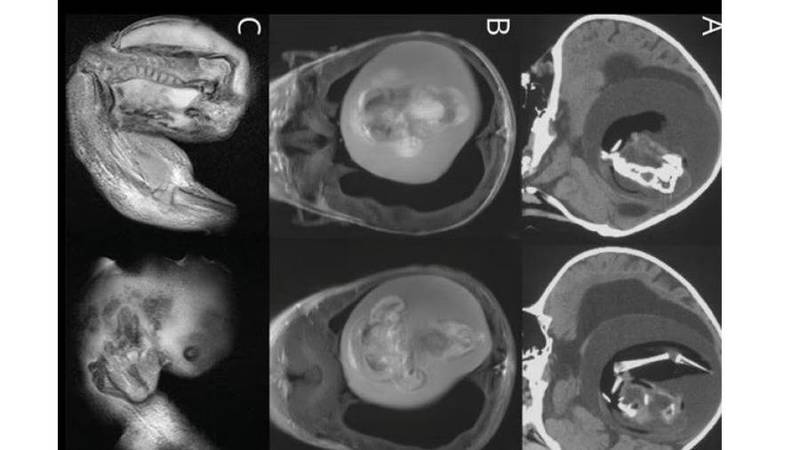

وكشفت الفحوصات الطبية، وجود جنين لم يولد بطول 4 بوصات، نمت أطرافه العلوية، وعظامه وأظافره، داخل جمجمة الصغيرة، ضاغطاً على دماغها، أزيل بعملية جراحية.

ويطلق على مثل هذه الحالة «جنين داخل الجنين»، وهو مصطلح طبي يصف الظواهر النادرة التي ترى فيها التوائم تندمج معاً في الرحم وينمو أحدهما جسدياً داخل الآخر.

وقال د. زونغزي لي، طبيب الأعصاب في مستشفى هواشان، جامعة فودان في مدينة شنغهاي الصينية، الذي عالج الفتاة: «إن سبب نمو الجنين داخل الجمجمة هو الحويصلات الجنينية غير المنفصلة؛ حيث نمت الأجزاء الملتصقة بالجزء الأمامي من دماغ الجنين المضيف وحوت الجنين الآخر أثناء انغلاق الصفيحة العصبية».

وكشفت الفحوصات الطبية، وجود جنين لم يولد بطول 4 بوصات، نمت أطرافه العلوية، وعظامه وأظافره، داخل جمجمة الصغيرة، ضاغطاً على دماغها، أزيل بعملية جراحية.

ويطلق على مثل هذه الحالة «جنين داخل الجنين»، وهو مصطلح طبي يصف الظواهر النادرة التي ترى فيها التوائم تندمج معاً في الرحم وينمو أحدهما جسدياً داخل الآخر.

وقال د. زونغزي لي، طبيب الأعصاب في مستشفى هواشان، جامعة فودان في مدينة شنغهاي الصينية، الذي عالج الفتاة: «إن سبب نمو الجنين داخل الجمجمة هو الحويصلات الجنينية غير المنفصلة؛ حيث نمت الأجزاء الملتصقة بالجزء الأمامي من دماغ الجنين المضيف وحوت الجنين الآخر أثناء انغلاق الصفيحة العصبية».